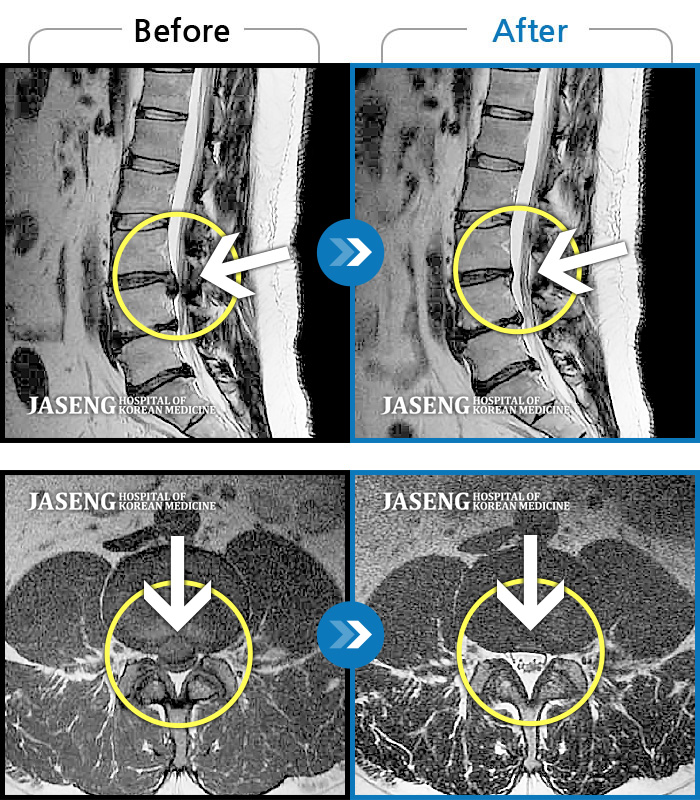

허리디스크

수원 · 김태성 원장

허리 통증과 우측 고관절~하지방사통이 심하여 활동하기 힘든 상태

촬영시기

2021.03.04 ~ 2021.10.06

2022.03.25